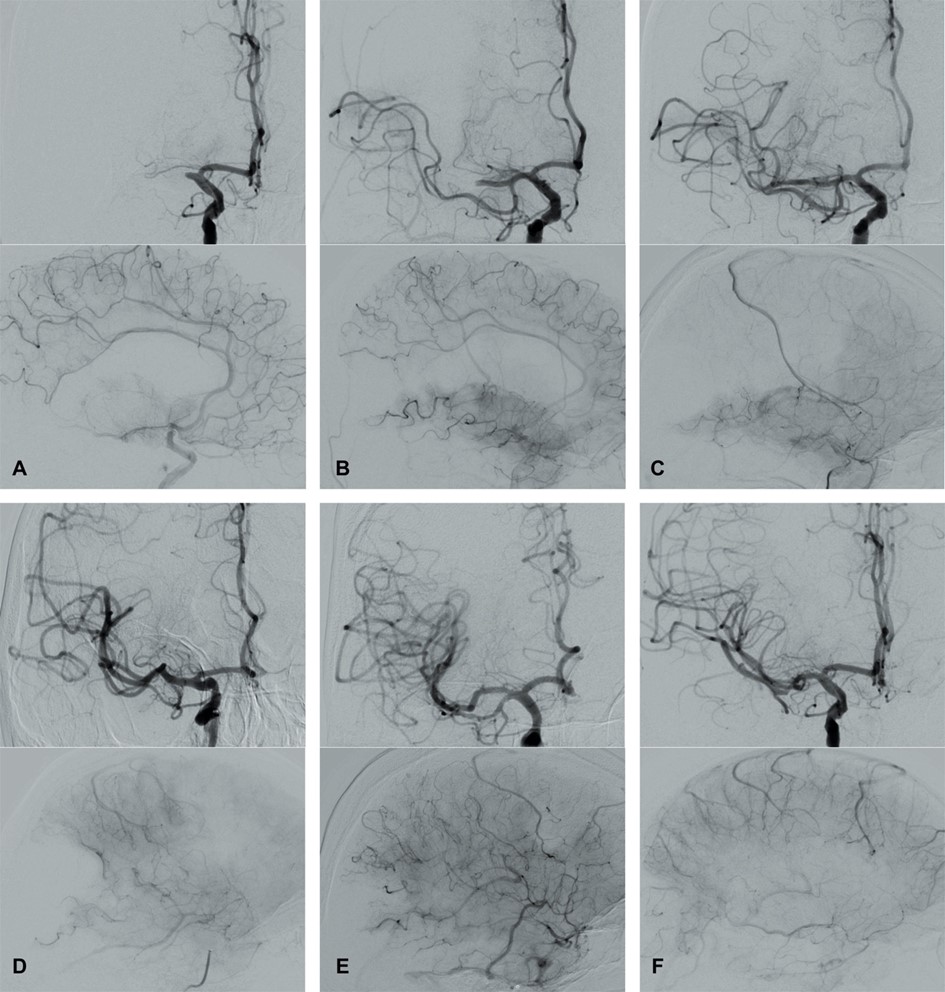

In 2003, Higashida et al. [96] developed the Thrombolysis in Cerebral Infarction (TICI) grading system for evaluating the therapeutic success of IVT (Fig. 4 and Table 3, Ref. [96, 97, 98, 99]). The TICI score is derived from the Thrombolysis in Myocardial Infarction (TIMI) risk score. TICI scores of 0 or 1 indicate no or limited perfusion, respectively. TICI scores of 2a and 2b describe anterograde reperfusion of less or more than half of the occluded target artery previously ischemic territory, respectively. A TICI score of 3 indicates complete reperfusion without any visible distal vessel occlusion. The TICI system has been adapted and modified (mTICI, which is commonly used in both the literature and routine clinical practice) to include an additional TICI 2c category indicating near-complete perfusion except for slow flow or distal emboli in several distal cortical vessels [97, 98]. An excellent reperfusion outcome is defined by mTICI scores of 2c/3. The HERMES collaborators described the expanded TICI (eTICI) score in 2019 [99]. MRS-shift analyses at 90 days after MT have suggested differences in outcomes depending on the percentage of recanalized brain tissue (Table 3). The eTICI has been found to be an independent predictor of outcomes.

Fig. 4.Modified Thrombolysis in Cerebral Infarction (mTICI) grading system for evaluating the therapeutic success of IVT. No perfusion of the right MCA - mTICI 0 (A). Antegrade reperfusion past the initial occlusion with only filling of a temporal branch of the right MCA - mTICI 1 (B). Antegrade reperfusion of only the superior division of the right MCA - mTICI 2a (C). Antegrade reperfusion of more than half of the previously occluded right MCA territory with persistent filling defect parieto-occipital - mTICI 2b (D). Near complete perfusion except for some distal emboli in several distal cortical vessels frontal and occipital - mTICI 2c (E). Complete antegrade reperfusion of the previously occluded right MCA - mTICI 3 (F).